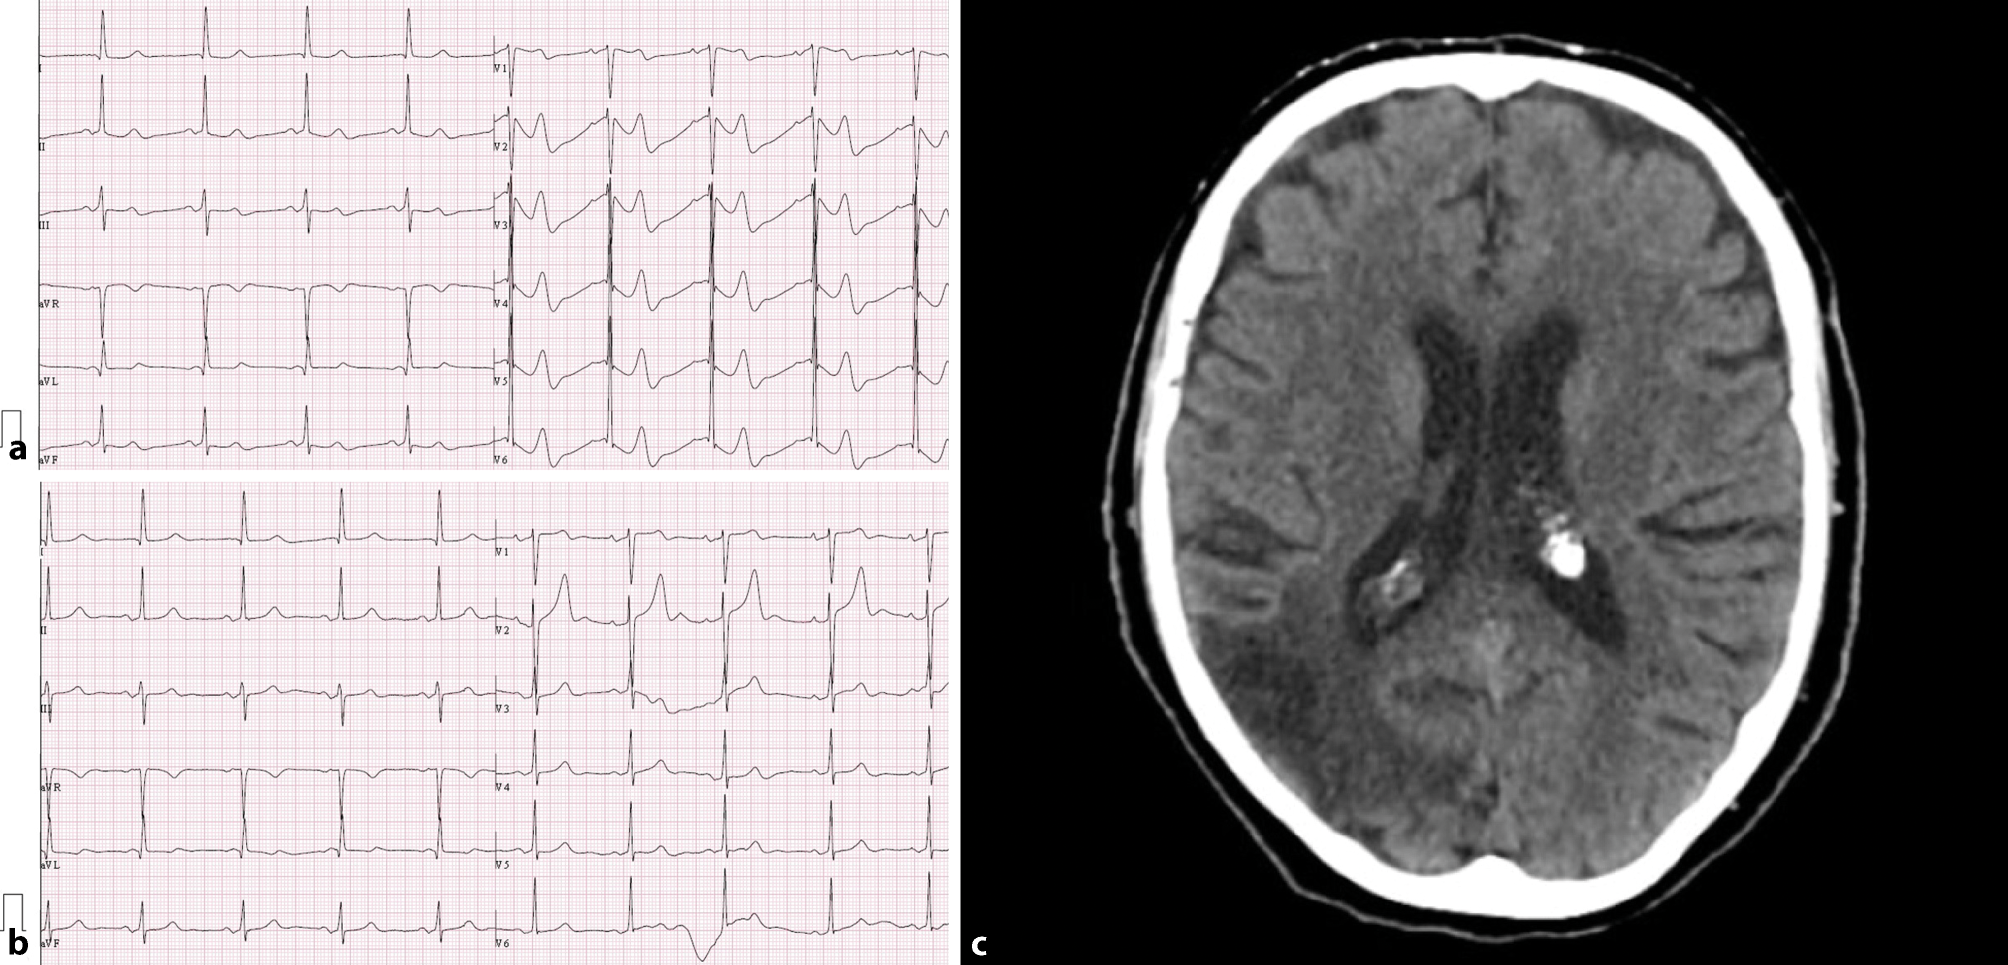

An 88-year-old female with a history of hypertension, dyslipidaemia and hypothyroidism but without known pre-existing heart disease arrived at the primary care emergency services with sudden confusion and agitation. On admission, electrocardiography (ECG) showed sinus rhythm (SR) with bizarre and distorted T waves associated with a prolonged QTc interval (589 ms) in leads V2–V6 (Fig. 1a). She was transferred to hospital, and ECG was repeated 2 h later, which showed a different pattern: SR and prolonged QTc interval without the previous ST-T changes (Fig. 1b). Cerebral computed tomography (CT) imaging identified an ischaemic area in the right temporal-occipital-parietal cortex (Fig. 1c). The patient was discharged after 7 days, with moderate mental confusion.

Electrocardiogram at a primary care emergency services and b hospital admission. c CT scan, at hospital admission, showing ischaemic area in right temporal-occipital-parietal cortex

Ischaemic strokes may be associated with ECG changes such as prolonged QT interval, ST-segment depression, T wave inversion or abnormal U waves. The precise mechanism has not yet been identified, but changes are usually transient [1]. There is a lack of evidence for prehospital ECG changes in acute stroke patients [2]. Recognition of this unusual pattern may point to a differential non-cardiac diagnosis and prevent delay in clinical decision-making and early treatment.